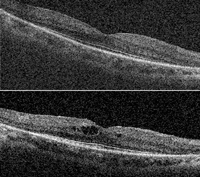

En la

Figura 48 se muestra un paciente con edema macular cistoideo en el ojo derecho en un contexto de retinosis pigmentaria ligada al X. Se aprecian los espacios quísticos intraretinianos con una MAVC de 0,2, y una mejora anatómica del edema tras 1 mes de tratamiento con acetazolamida por vía oral. Su MAVC pasó a ser de 0,4.

Figura 48. Retinosis pigmentaria ligada al X. Edema macular cistoideo en ojo derecho. A) Espacios quísticos intraretinianos. B) Mejora anatómica del edema tras 1 mes de tratamiento con acetazolamida por vía oral.